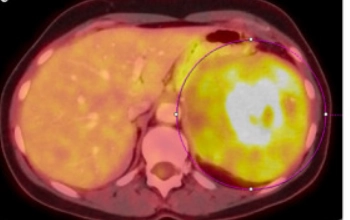

• Di căn lách (Splenic metastases)